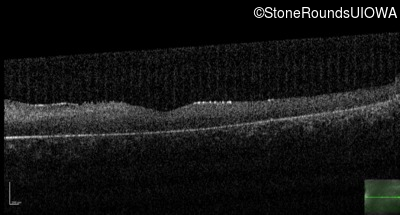

Optical Coherence Tomography - Left - 10/160 sc

Exemplar / OCT Stack